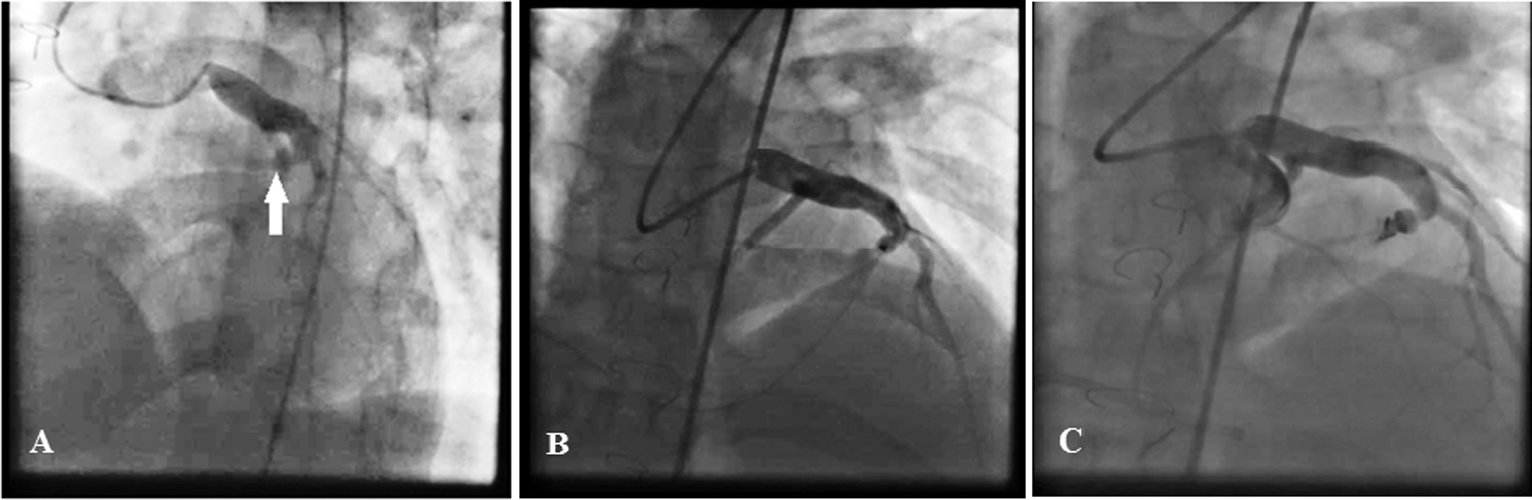

Coronary angiography revealed a dilated left coronary artery proximal to the LAD and also a large CAF from the septal branch of the LAD to the RVOT. No detailed follow-up data during postoperative years were available, but iatrogenic fistula formation following surgery is a possibility. During cardiac catheterization, there was a significant O2 step up in the RVOT, prompting the medical team to proceed with fistula occlusion.

First, the LAD was wired to the RVOT with a 0.014 guidewire, and snaring was done via the right femoral vein access. Then an 8-F right Judkins guiding catheter was introduced via the femoral vein right access toward the distal part of the CAF. The 0.014 guidewire helped the operator to negotiate the 8-F right Judkins guiding catheter to the distal part of the CAF and also to stabilize the catheter during the release of the occluder device. Thereafter, a detachable coil device (5 × 4 mm Duct Occluder pfm, Nit-Occlud PDA, pfm medical ag, Germany) was inserted in the distal part of the CAF, with a mild residual shunt (Fig. 2). Fortunately, at 6 months’ follow-up, the patient was asymptomatic. The echocardiogram showed no residual shunt flow and a Qp/Qs ratio of 1.1:1.

Figure 2: The coronary angiogram reveals a dilated left coronary artery proximal to the left anterior descending and also a large coronary artery fistula from the septal branch of the left anterior descending (white arrow) to the right ventricular outflow tract (Fig. A). The left anterior descending artery was wired to the right ventricular outflow tract with a 0.014 guidewire, and snaring was done via the right femoral vein access (Fig. B). Subsequently, an 8-F right Judkins guiding catheter was introduced through the right femoral vein access toward the distal part of the coronary artery fistula. Finally, a detachable coil device (5 × 4 mm Duct Occluder pfm, Nit-Occlud, pfm medical ag, Germany) was inserted in the distal part of the coronary artery fistula, with a mild residual shunt (Fig. C)